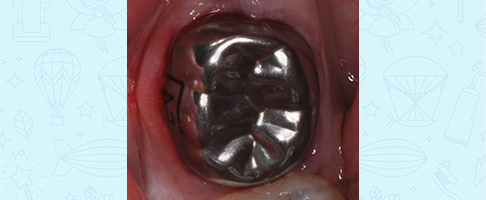

Лечение кариеса, восстановление зуба коронкой

Лечение кариеса молочного зуба, восстановление коронкой и герметизация фиссур с применением закиси азота

Лечение пульпита молочного зуба, восстановление коронкой

Лечение пульпита молочного зуба, восстановление коронкой

Лечение пульпита молочного зуба, восстановление коронкой